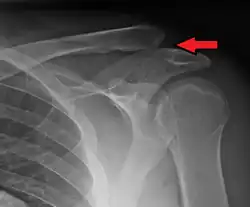

An Xray showing a separated shoulder. Notice the separation between the end of the collarbone and the scapula.

X-ray indicates a separated shoulder when the acromioclavicular joint space is widened (it is normally 5 to 8 mm).[9]